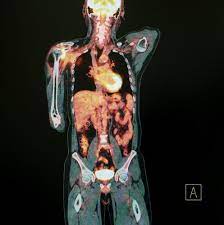

Clinical Proteomics For Prostate Cancer Understanding Prostate Cancer Pathology And Protein Biomarkers For Improved Disease Management Clinical Proteomics Full Text from media.springernature.com Several signs can point to a prostate cancer that has come back or spread, including Early prostate cancer usually causes no symptoms or signs. For patients with a rising psa level after surgery or radiation for localized prostate cancer, the estimate of total psa alone is an imperfect predictor of a positive bone scan. Learn more about the signs and symptoms here. Weak or interrupted urine flow or the need to strain to empty the bladder. Both acid phosphatase and psa levels decrease after treatment and increase with recurrence, but psa is. The prostate is a gland in the male reproductive system that surrounds the urethra just below the bladder. The symptoms and signs of prostate cancer may include:

5 warning signs are bone pain, compression of the spine, painful urination, erectile dysfunction, and blood in the urine. 29 prostate cancer in younger patients 30 clinical trials 31 supplementary interventions 33 what are the possible side effects of treatment? Some prostate cancer grows too slowly to cause any problems or affect how long you live. Here, cancer cells form from gland cells that line the sacs. This may be related to the fact that type 2 diabetes is associated with reduced circulating prostatic levels of androgens 3. Up to 30% of men will have what is termed a psa recurrence after initial treatment (which is also called biochemical recurrence or biochemical failure). Prostate cancer can recur locally (in the area immediately surrounding the prostate) or. For patients with a rising psa level after surgery or radiation for localized prostate cancer, the estimate of total psa alone is an imperfect predictor of a positive bone scan. Most prostate cancers are slow growing. Prostate cancer that's more advanced may cause signs and symptoms such as However, the relative survival rates remain high; Psa is concentrated in prostatic tissue, and serum psa levels are normally very low. The most common first sign of recurrent prostate cancer is a rise in the psa level in the blood, making regular psa tests all the more important in measuring the progress of treatment and checking for signs of recurrence.